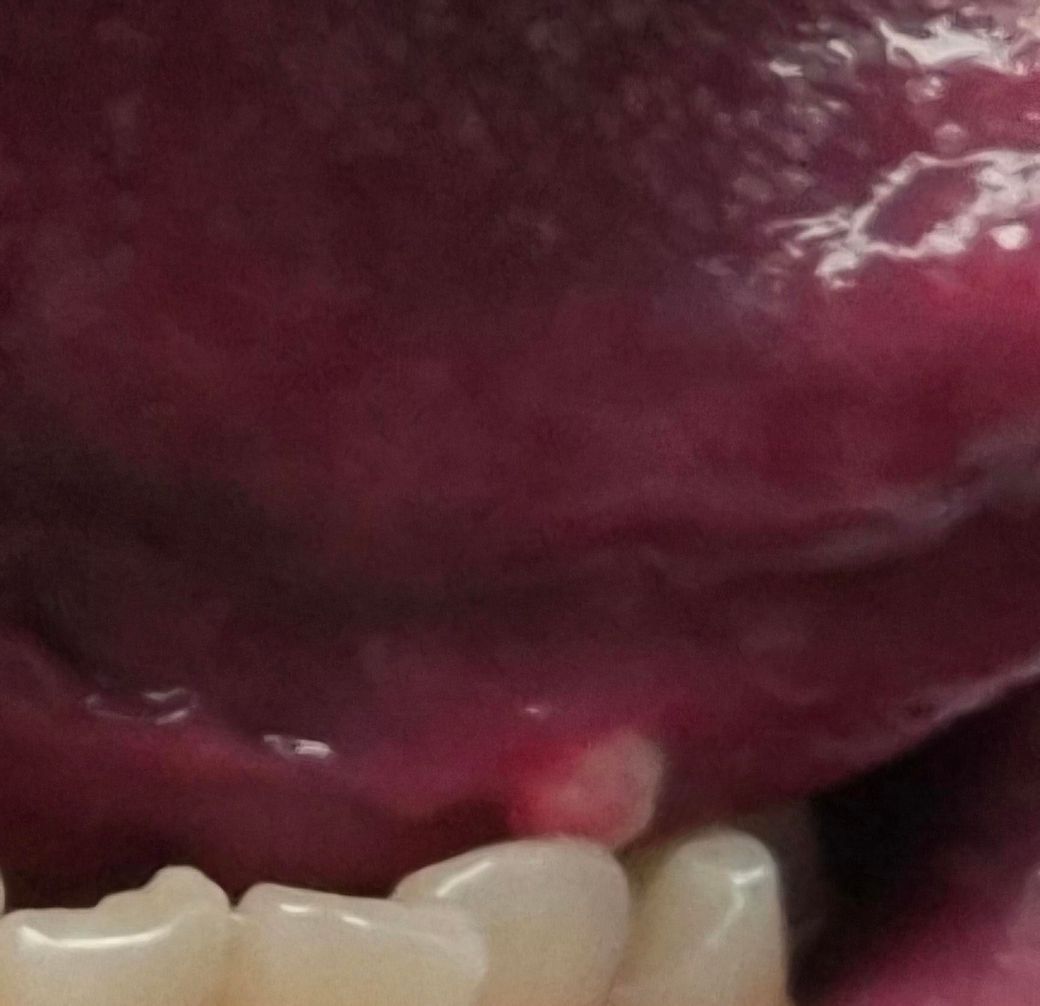

3일전부터 혀 밑쪽에 쌀알? 같은 크기로 뭔가 튀어나와있습니다. 하얗게 되어있어서 첨엔 구내염인가 했는데, 저 부분이 쌀알 마냥 튀어나와있어요. 저게 뭘까요? 병원 가봐야 할까요

혀 밑에 쌀알처럼 튀어나온 하얀 돌기는 혀 밑에 있는 타액선에서 발생할 수 있는 타액선 결석일 가능성이 있습니다. 타액선 결석은 타액이 굳어서 생기는 작은 덩어리로, 보통 혀 밑이나 입안의 다른 부위에 발생할 수 있어요

이 경우, 결석이 타액의 흐름을 방해해 입 안에 불편함을 느낄 수 있으며, 때로는 결석이 염증을 일으켜 부풀어 오르거나 하얗게 보일 수 있죠

다른 가능성으로는 구내염이나 혀의 염증이 있을 수 있습니다. 구내염은 입안의 점막에 발생하는 염증으로, 작은 물집이나 튀어나온 형태로 나타날 수 있으며, 이 또한 하얗게 보일 수 있어요. 이 경우 통증이나 불편감이 동반될 수 있습니다. 만약 증상이 지속되거나 악화되면 병원에 가서 진단을 받는 것이 좋습니다. 특히 결석이 의심되는 경우, 치료 방법으로 결석을 제거하거나 염증을 완화하는 치료가 필요할 수 있죠

따라서, 증상이 3일 이상 지속되고 불편함이 심하다면 치과나 이비인후과 진료 및 상담을 받는 것이 중요합니다